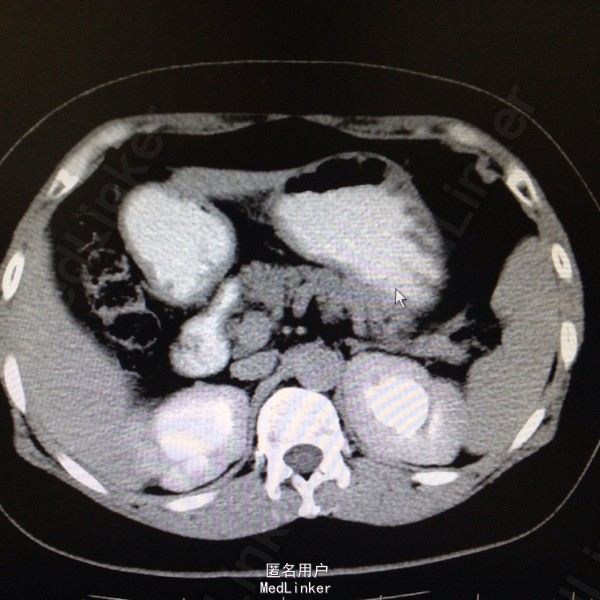

47岁女患。 病史:患者6年前因宫颈癌行全子宫及双侧附件切除。盆腔淋巴结清扫。腹主动脉旁淋巴结活检术。后又行局部放疗。因双肾积水来我科。患者自述平时轻微排尿困难,尿线细。

双肾区无叩击痛,双输尿管走形区无压痛。耻骨上区隆起,叩诊浊音。排尿后留置尿管引流尿液400ml。 辅助检查:肌酐99。 ct:双肾及输尿管积水。 留置尿管后一周泌尿系彩超:双肾积水明显减轻。具体见图片。

诊断:双肾及双输尿管积水 神经源性膀胱 给予患者留置尿管后1周行泌尿系彩超检查肾积水减轻。